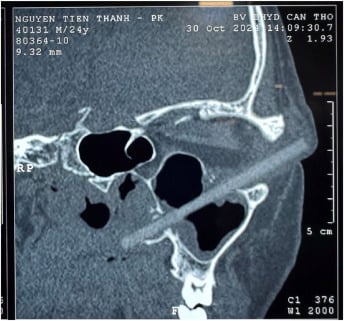

แพทย์จึงทำการตรวจสอบและพบว่าลูกตาเขาไม่ได้มีปัญหาอะไร ทว่ามุมตาซ้ายของเขามีอาการบวมและมีหนองขนาดเล็กไหลออกมา เมื่อตรวจสอบดีๆพบว่ามีเศษอะไรบางอย่างขนาดประมาณ 9 เซนติเมตรติดอยู่ เมื่อดีๆก็พบว่าเป็นเศษตะเกียบ ซึ่งทะลุผ่านเนื้อเยื่ออ่อนด้านนอกของเบ้าตาซ้าย ขึ้นไปจนถึงผนังด้านบนของไซนัสแม็กซิลลา และทำลายผนังด้านข้างของจมูก

โดยแพทย์ได้นำเศษตะเกียบไม้ออกมาได้อย่างปลอดภัยด้วยการผ่าตัดและส่องกล้องเข้าไปเพื่อให้มั่นใจว่าไม่มีวัตถุใดหลงเหลืออยู่ จากการตรวจสอบพบว่าตะเกียบนั้นสกปรกคาดว่าใช้บริโภคอาหารก่อนจะติดอยู่ในตาของชายคนดังกล่าว แพทย์ยังระบุด้วยว่าชายคนดังกล่าวโชคดีมากที่ตะเกียบไม่ได้แทงลูกตาเขา